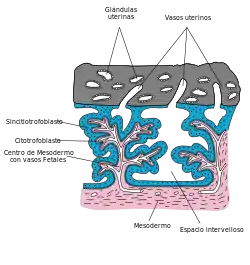

Otro sincitio importante en vertebrados está en la placenta de los mamíferos placentarios. La conversión del citotrofoblasto —capa de Langhans— en sincitio es una forma fisiológica para regenerar la placenta. Cuando se implanta el embrión está rodeado únicamente de elementos citotrofoblásticos. Sin embargo, algunos estudios científicos en humanos[33][34] demostraron que en el día 14 después de la ovulación, cuando debería producirse la menstruación en condiciones de no - embarazo, la hemorragia periovular que ocurre induce la transformación en sincitio del trofoblasto inmaduro, debido a reacciones inmunitarias.[35]

Cuando se forma la placenta, el estrato de Langhans predomina sobre el sincitio. A medida que la placenta madura, la relación se invierte. La distribución característica de la circulación de la sangre por los vasos fetoplacentarios determinan una mejor irrigación tanto del estrato de Langhans como del sincitio, facilitando el intercambio entre la circulación fetal y el espacio intervelloso, lo que constituye una adaptación a la mejor oxigenación del feto en el embarazo.[36]

Las células embrionarias, sin membranas que las separen, forman una barrera multinucleada.[35][36] El sincitio placentario tiene además otras funciones. Presenta gran cantidad de organelos citoplasmáticos, especialmente en las últimas etapas de desarrollo fetal, indicando un alto metabolismo. También es un gran depósito de hierro, que obtiene del plasma materno.[37] Además se ha demostrado mediante estudios inmunohistoquímicos que el sincitio es el principal lugar donde se forma la gonadotrofina coriónica humana (hCG). Así mismo, como se ha detectado en el huevo recién implantado en el cual el trofoblasto aún no ha madurado, se piensa que también se origina en el citotrofoblasto. El sincitio produce gran cantidad de proteínas placentarias que vierte a la sangre materna. Algunos afirman que evitan el rechazo del feto por procesos inmunes naturales y evitan la coagulación sanguínea en los espacios intervellosos, aunque otros piensan que no cumplen ninguna función. Estas proteínas son liberadas por factores liberadores producidos por la propia placenta, que de este modo actúa en forma autócrina. La producción de proteínas se mantiene en permanente aumento durante todo el embarazo.[35]

Cuando el embarazo acaba, el citotrofoblasto se disgrega y el sincitio se vuelve extremadamente delgado, produciendo un estrecho acercamiento entre la sangre materna y la fetal, hasta el punto que en algunos sitios quedan apenas separadas por el endotelio de los capilares fetales. Estos puntos se conocen como membranas vásculo-sincitiales, que se ubican por debajo del sincitio y lo separan del capilar fetal —semejantes a la del glomérulo renal—. Estas membranas están especializadas en filtrar la sangre; no se encuentran en placentas inmaduras, ni en maduras patógenas en las que el trofoblasto no ha madurado, por lo que puede considerarse que la placenta se divide en dos superficies con funciones distintas: la que corresponde a la aposición endotelio-corial —filtrante— y otra constituida por el sincitio —con función metabólica—.[35]